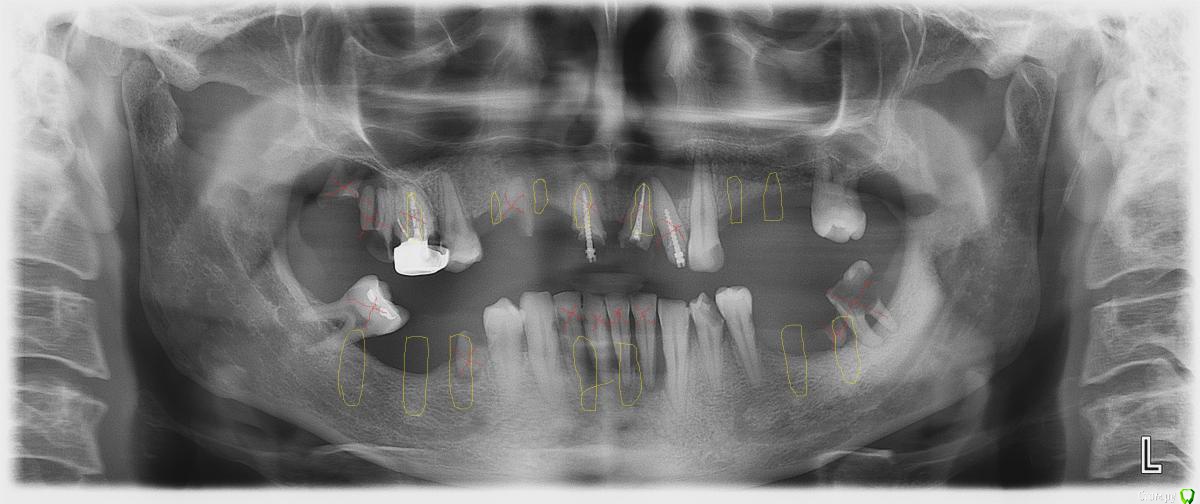

-SAE-Dantist_32 Опубликовано 17 июля, 2015 Поделиться Опубликовано 17 июля, 2015 не знаю как поступить с 1.1 2.1 сносить? Ссылка на комментарий

krokomot Опубликовано 17 июля, 2015 Поделиться Опубликовано 17 июля, 2015 Сносите. При их протезировании мало того, что коронки получатся оч длинными так еще и широкими потому как расстояние между корнями не благоприятствует их протезированнию. Поэтому в лучшем случае будут проблемы с десной. Ссылка на комментарий

-SAE-Dantist_32 Опубликовано 17 июля, 2015 Автор Поделиться Опубликовано 17 июля, 2015 а как быть с 3.3?c одной стороны жалко с другой понемаеш что нужно сносить) Ссылка на комментарий

krokomot Опубликовано 17 июля, 2015 Поделиться Опубликовано 17 июля, 2015 Планируется имплантация? Ссылка на комментарий

-SAE-Dantist_32 Опубликовано 17 июля, 2015 Автор Поделиться Опубликовано 17 июля, 2015 да в планах имплантация,правда не придумал карту сколько куда) Ссылка на комментарий

Doc.IQ Опубликовано 17 июля, 2015 Поделиться Опубликовано 17 июля, 2015 При имплантировании тотально удалился бы..если имплантация не планируется оставил бы 16,23,34,35,43,44..остальное на вылет.. Ссылка на комментарий

krokomot Опубликовано 17 июля, 2015 Поделиться Опубликовано 17 июля, 2015 Если имплантация все сомнительное вон и мешающее Ссылка на комментарий